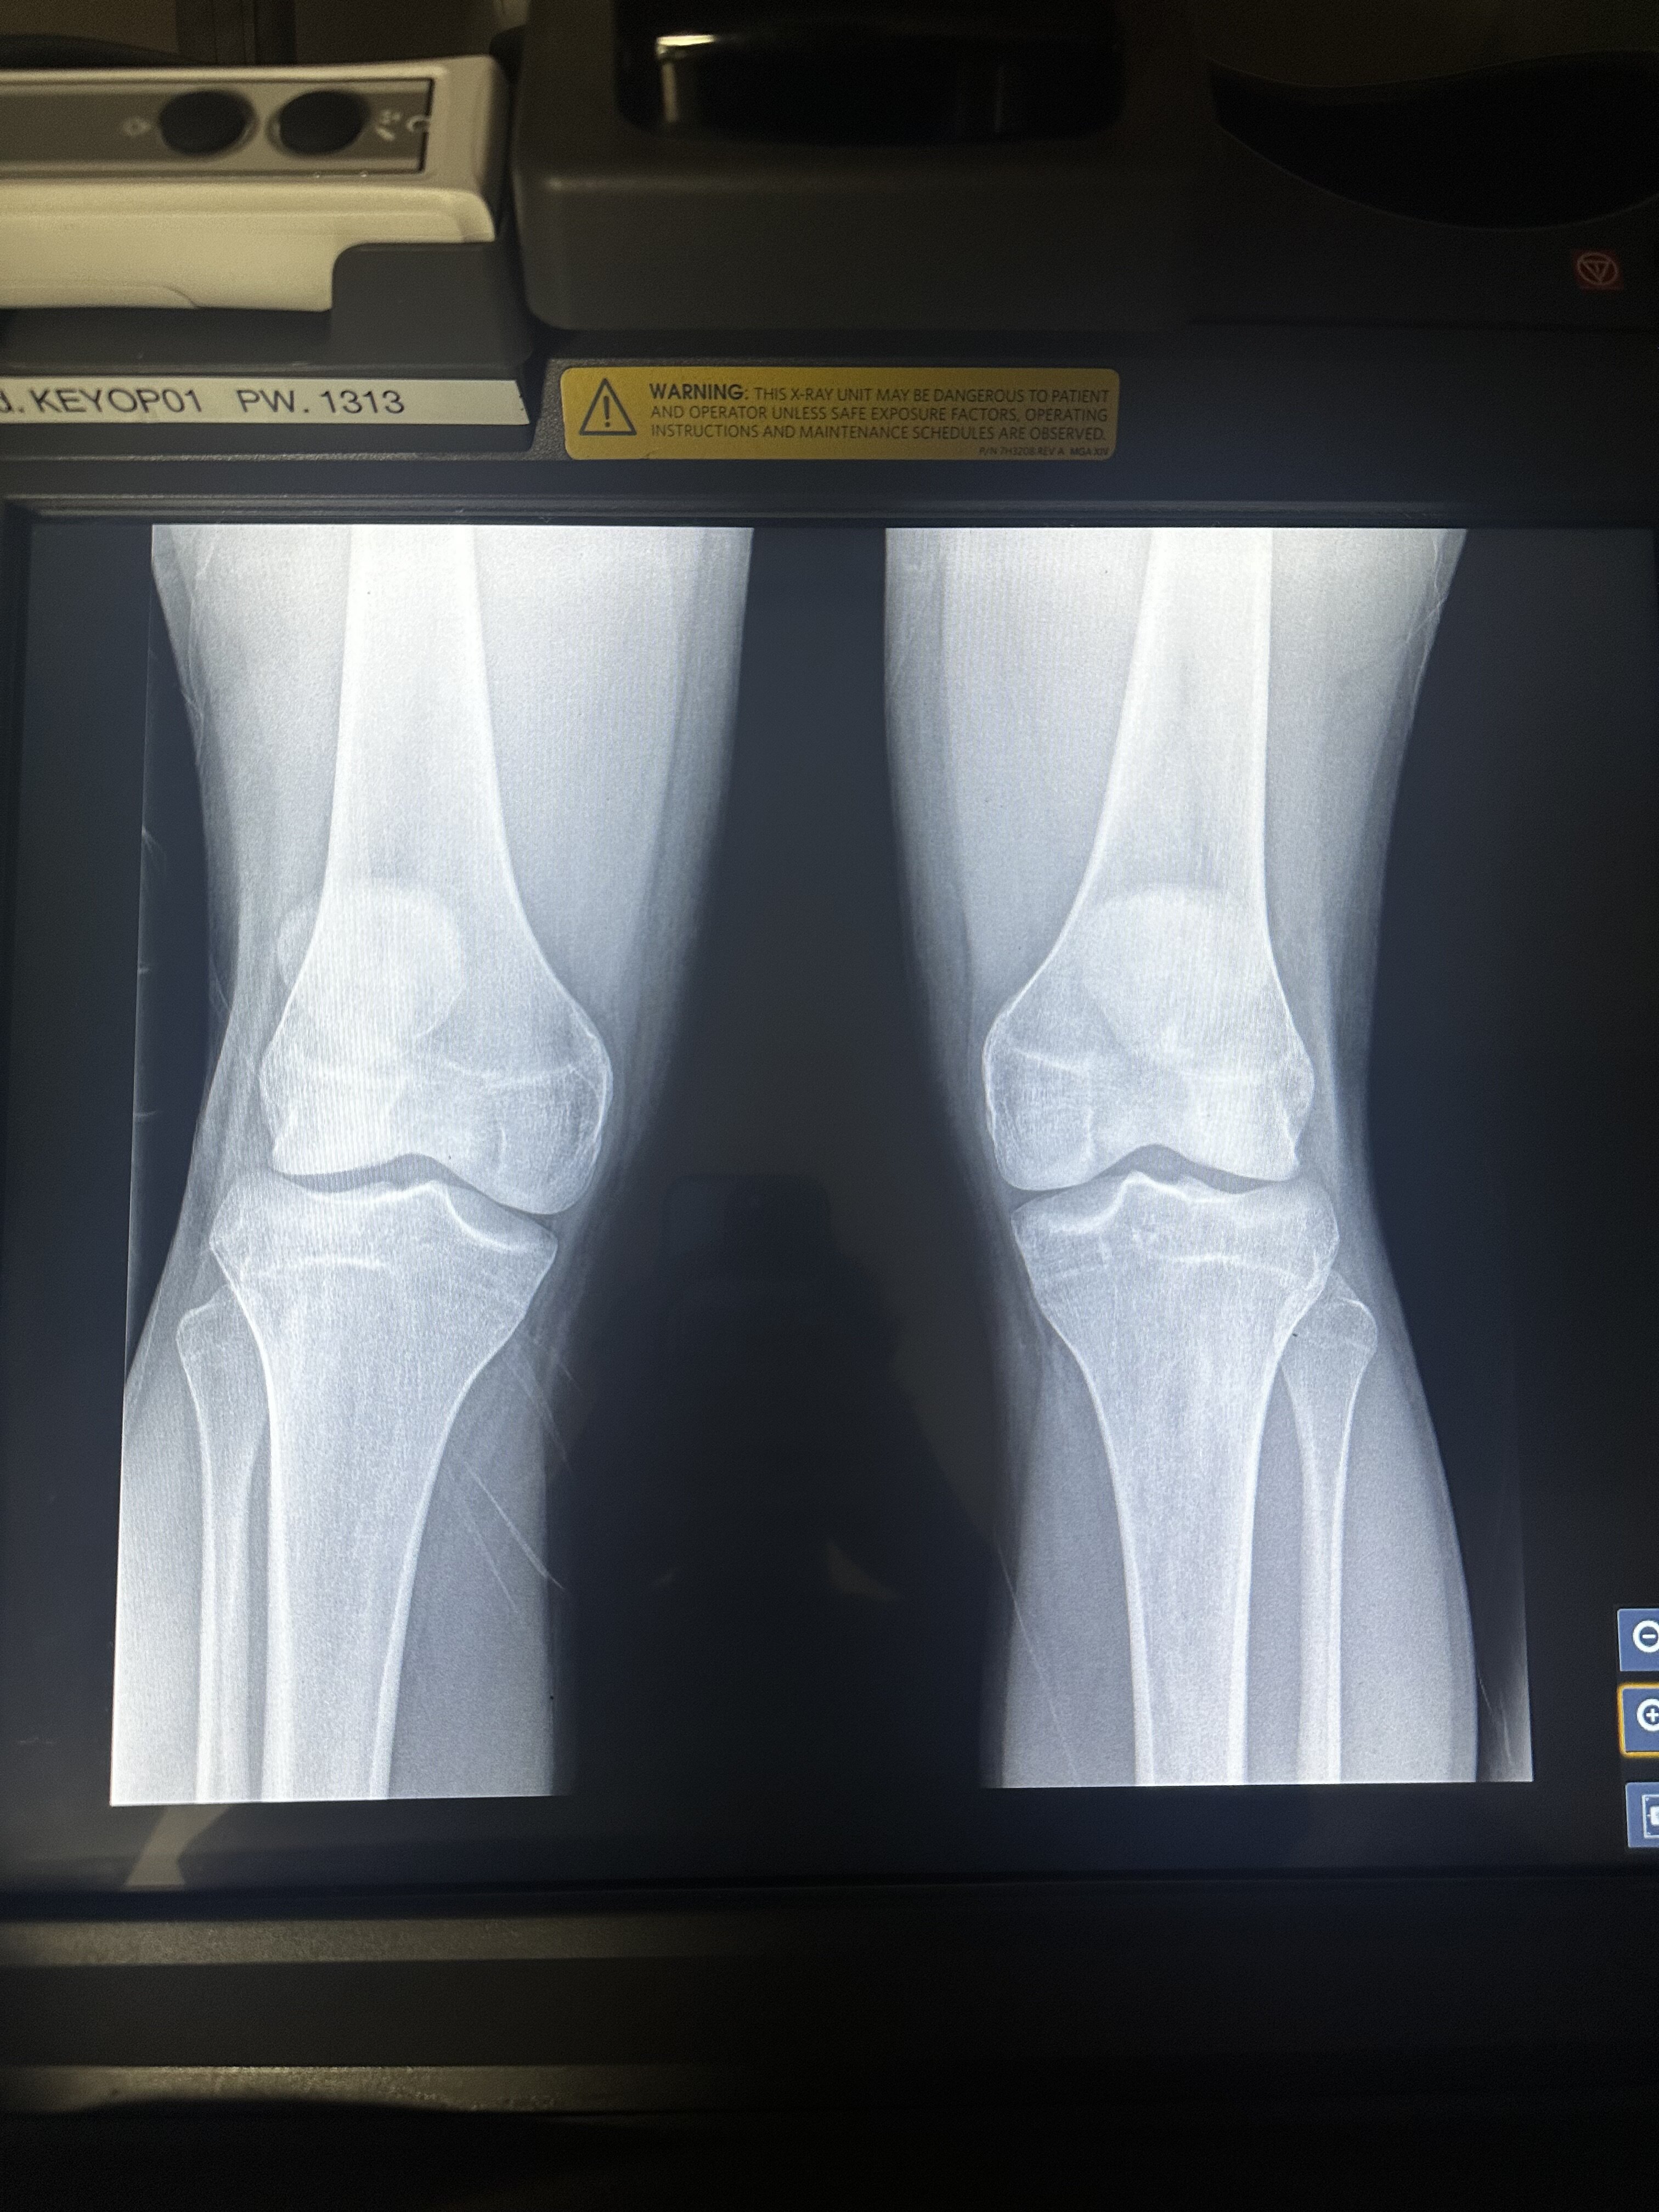

I did a regular xray on my bones, can someone tell me if my growth plates are still open. I have 2 different types of color setting of the xray.

Looking at them, it looks like they're still open but very close to fusing. You an see the white lines on each bone so they are not quite fused.

You see the difference? Same goes for your other bones.

closed 95% don't expect any growth without ai+HGH

probably hgh tbh, but you likely won't gain any more than 1 or 2 inches if any. Like the other guy said, they are 95 percent closed if not newly closed. Wish you luck.

Hands closed rest still kinda open gonna close in max a year id say

Slightly, I guess that you are 16/17 through the x ray

they are but their about to close